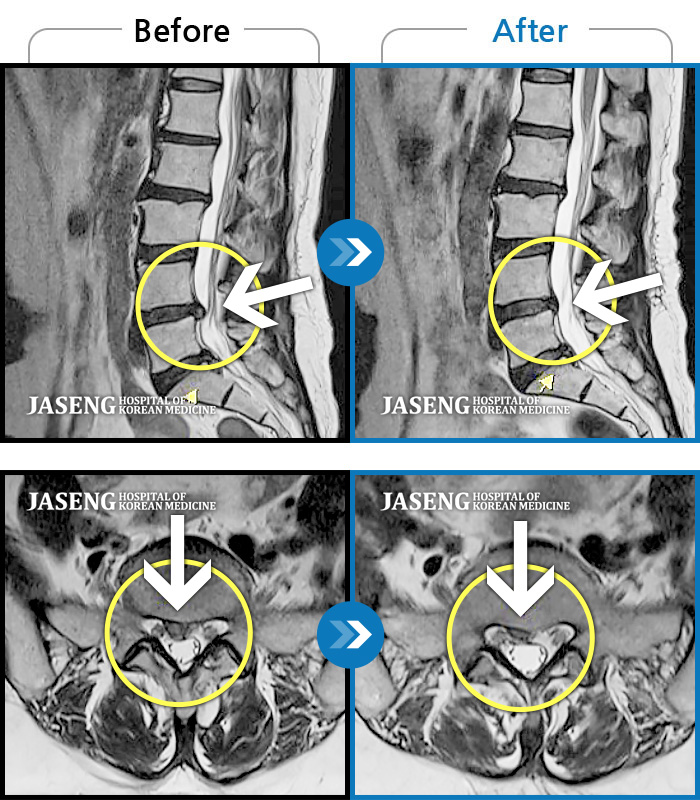

허리디스크

광주 · 김동은 원장

허리부터 골반 및 우측 허벅지에서 발가락까지 묵직한 통증과 저림 발생하여 내원하셨습니다.

촬영시기

2022.07.22 ~ 2025.08.18

2025.08.22